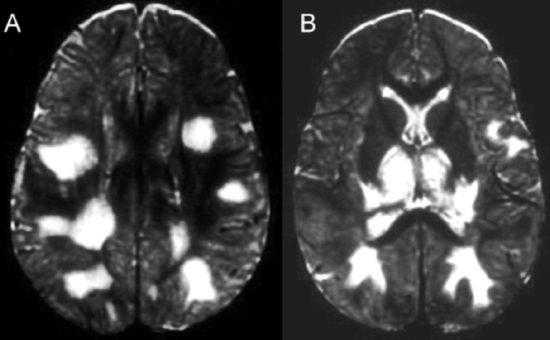

Рисунок 1 | Асимметричные области патологически повышенного МР сигнала в медиальных отделах обеих височных долей, больше выраженные в корковом веществе

Рисунок 2 | В последовательности DWI у того же пациента определяются области повышения сигнала в обоих лобно-височных областях. ИДК подтвердила ограничение диффузии